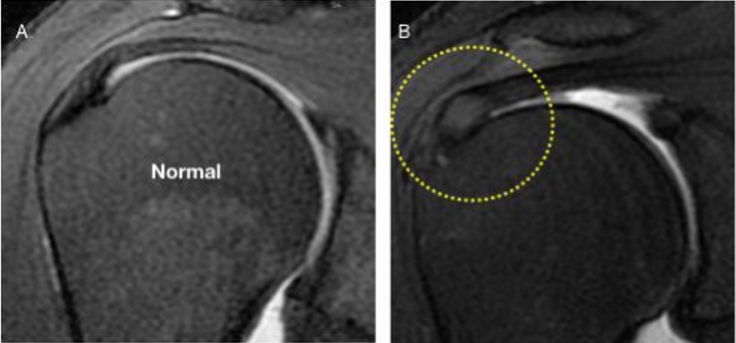

Q. Elige la respuesta correcta respecto a la siguiente imagen:

Rotura parcial del tendón supraespinoso en su cara bursal mayor del 50 %